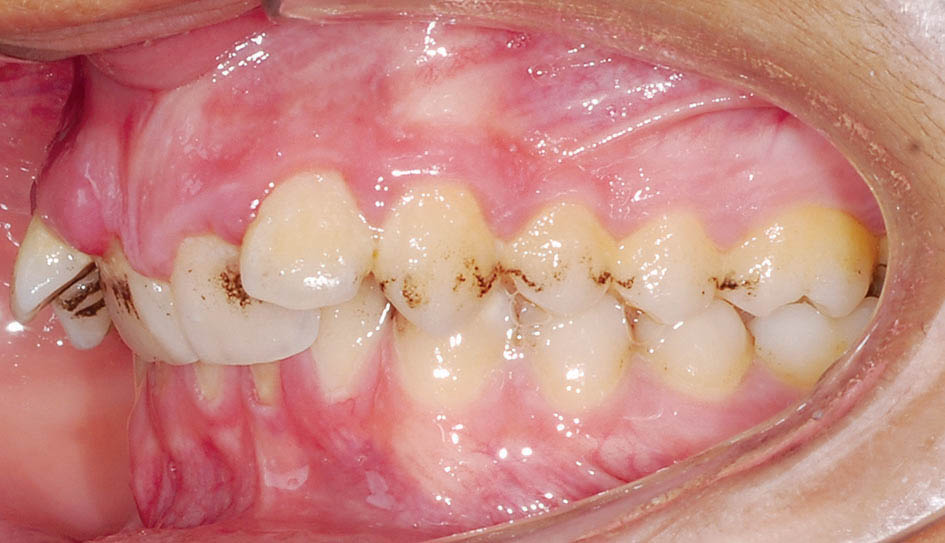

اگر قوس بالا تنگتر از نرمال باشد (شکل 75-3) منجر به کراس بایت خلفی پالاتالی میشود. اگر هر دو طرف تنگ باشد کراس بایت خلفی دو طرفه پالاتالی و اگر یک طرف تنگ باشد کراس بایت خلفی یک طرفه پالاتالی میگوییم.

شکل 75-3: کراس بایت خلفی

به حالتی اطلاق میشود که دندانهای خلفی پایین (یک یا چند تا، یک سمت یا هر دو سمت) لینگوالی بشوند. اصطلاح دیگر آن کلاپس قوس پایین، پیستون بایت، یا سندرم Brodie است.

وقتی خلفیهای بالا کاملاً در باکال یا لینگوال خلفیهای پایین قرار گیرد گفته میشود (شکل 76-3).

شکل 76-3: بایت scissors در سمت راست